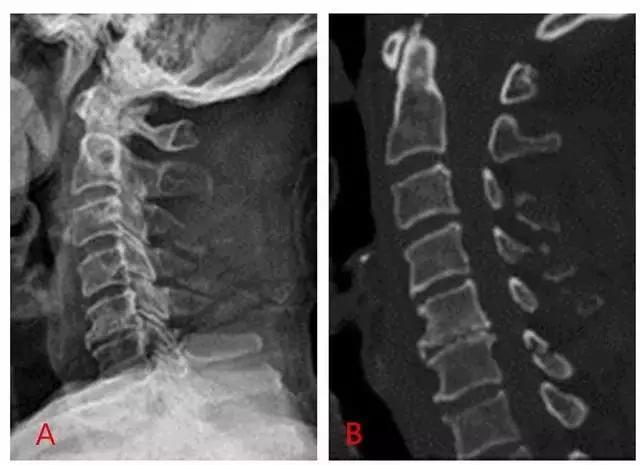

4. Clay-shoveler 骨折

铲土者骨折,是发生在低位颈椎或高位胸椎棘突(C7 或 T1 最多见)的一种撕脱骨折。损伤是由于工人企图向上扔一满铁铲的泥土,但是泥土粘住铁铲,引起一个突然的屈曲力量反作用于颈部引起的损伤,故命名。

图为铲土者骨折(C3~C5)的平片(A)及 CT 扫描(B)(来源:Radiopaedia)